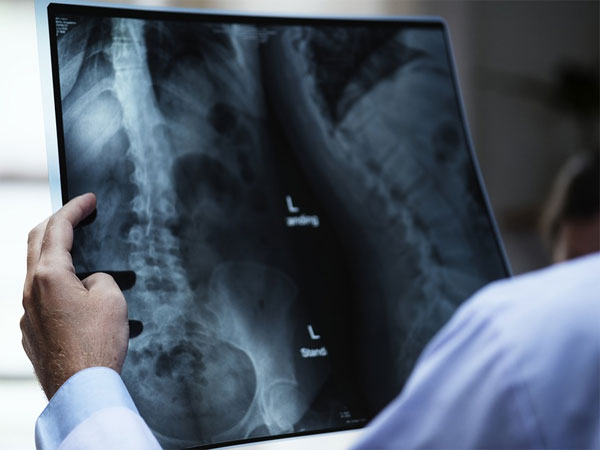

Vanishing Bone Disease: All You Need To Know About The Rare Disorder

Vanishing Bone Disease or Phantom Bone Disease/Gorham Stout Disease/Progressive Massive Osteolysis is a skeletal disease, which is characterized by destructive or uncontrolled proliferation of vascular/lymphatic channels within a bone and also its surrounding soft tissue.

The most commonly affected bones are - shoulder, pelvis, jaw, ribs, spine, skull and collarbone. It can be characterized by pain, external swelling and deformity of the area surrounding the bone.

Bones involved also show a gradual reduction in the mass. This makes the bone weaker overtime, making it more vulnerable to severe bone damage.